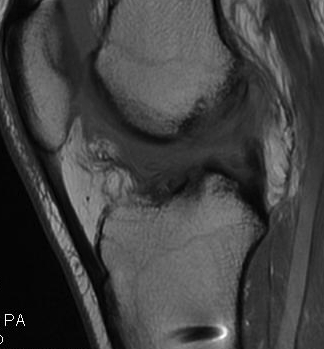

Graft rupture best seen on T1